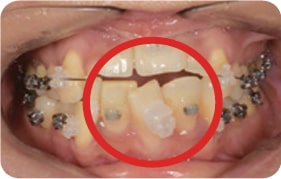

Case 4

2017. 08. 04

2017. 12. 15

2018. 02. 10